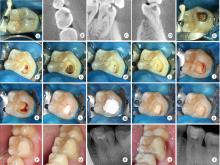

郑颖, 陈雪姣, 王倩. 单向滤膜减压保髓新技术用于不可复性牙髓炎活髓保存治疗1例[J]. 中华口腔医学杂志, 2024, 59(1): 85-88.